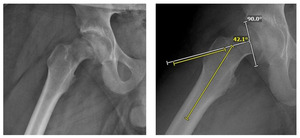

Radiographs including AP pelvis, AP and lateral (frog leg) of both hips demonstrated skeletal maturity at the stage of Risser 1 with closed triradiate cartilage and open proximal femoral physis of both hips (Figure 1). The right hip revealed a slipped capital femoral epiphysis with a disrupted Klein’s line and Southwick angle of 42.1 (Figures 2-7). Thus, due to his radiographs as well as his two weeks of inability to bear weight, he was found to have an acute-on-chronic unstable SCFE on the right.